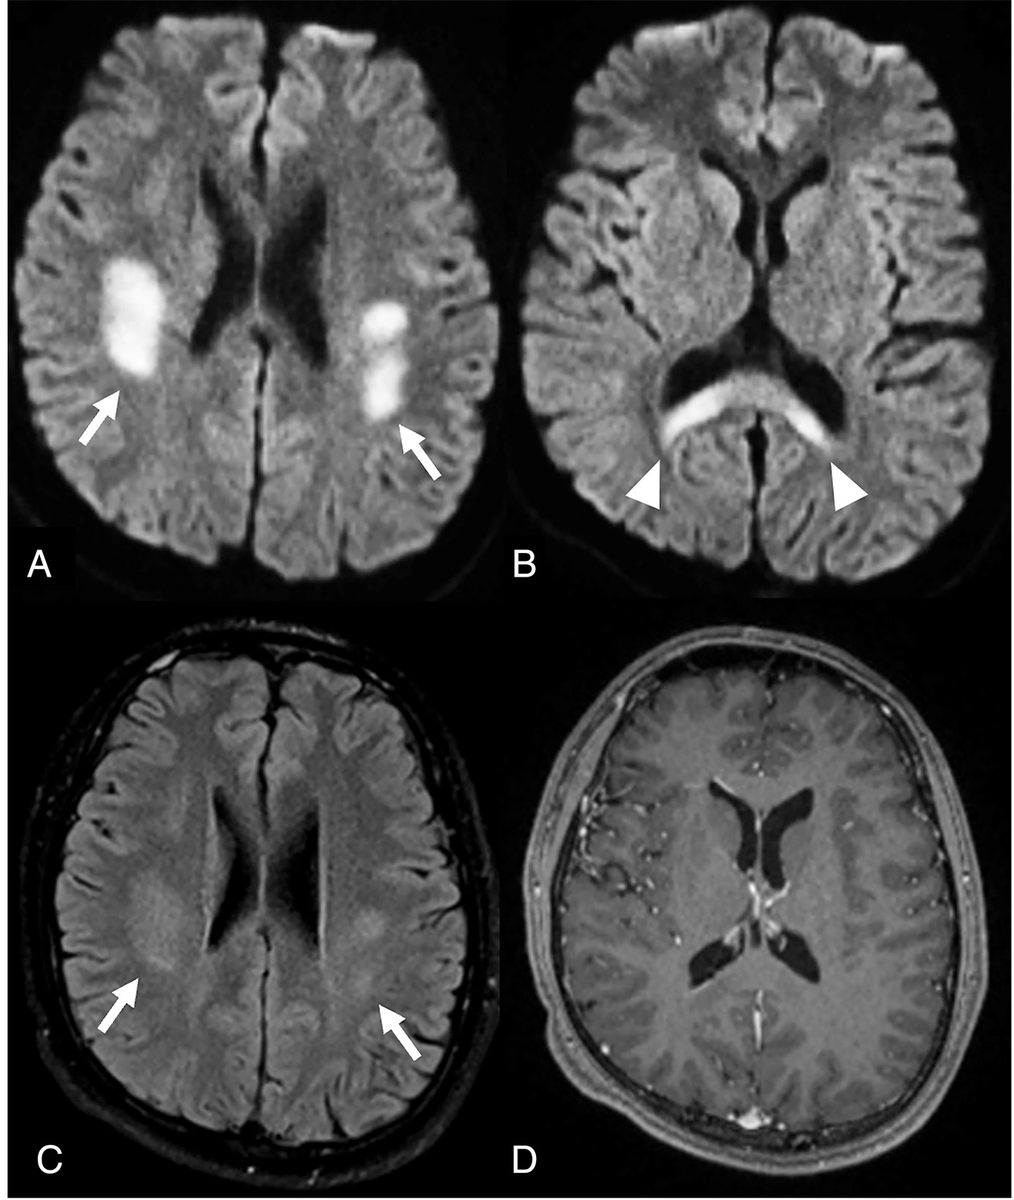

From the July-September 2025 Issue of #Neurographics: Recurrent Stroke-Like Episodes in X-Linked Charcot-Marie-Tooth Type 1 Disease: Characteristic Brain MRI Findings ow.ly/W9vt50WITmU